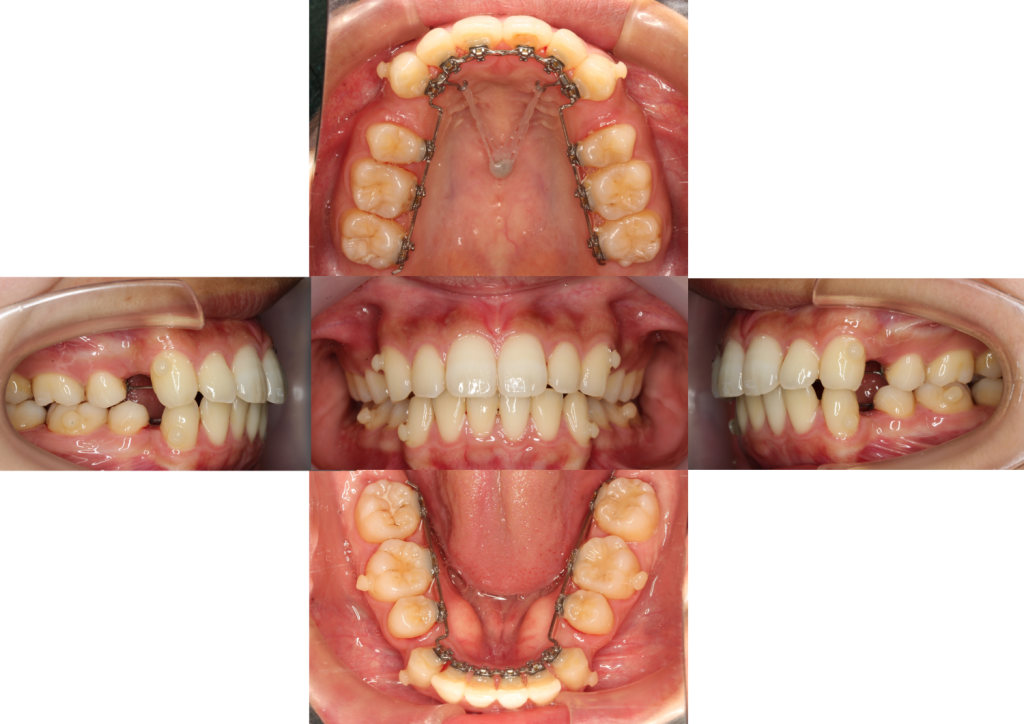

上下歯のガタツキがなくなりました。

次は前歯を後ろに引っ張っていきます。こちらの患者様は上顎にTADsと言う小さいインプラントをつけ、

TADsを固定源にゴムで前歯を後ろに引っ張っています。